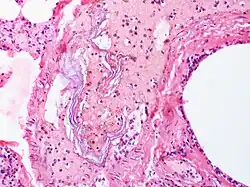

| Intravascular squames are present in this example of amniotic fluid embolism. | |